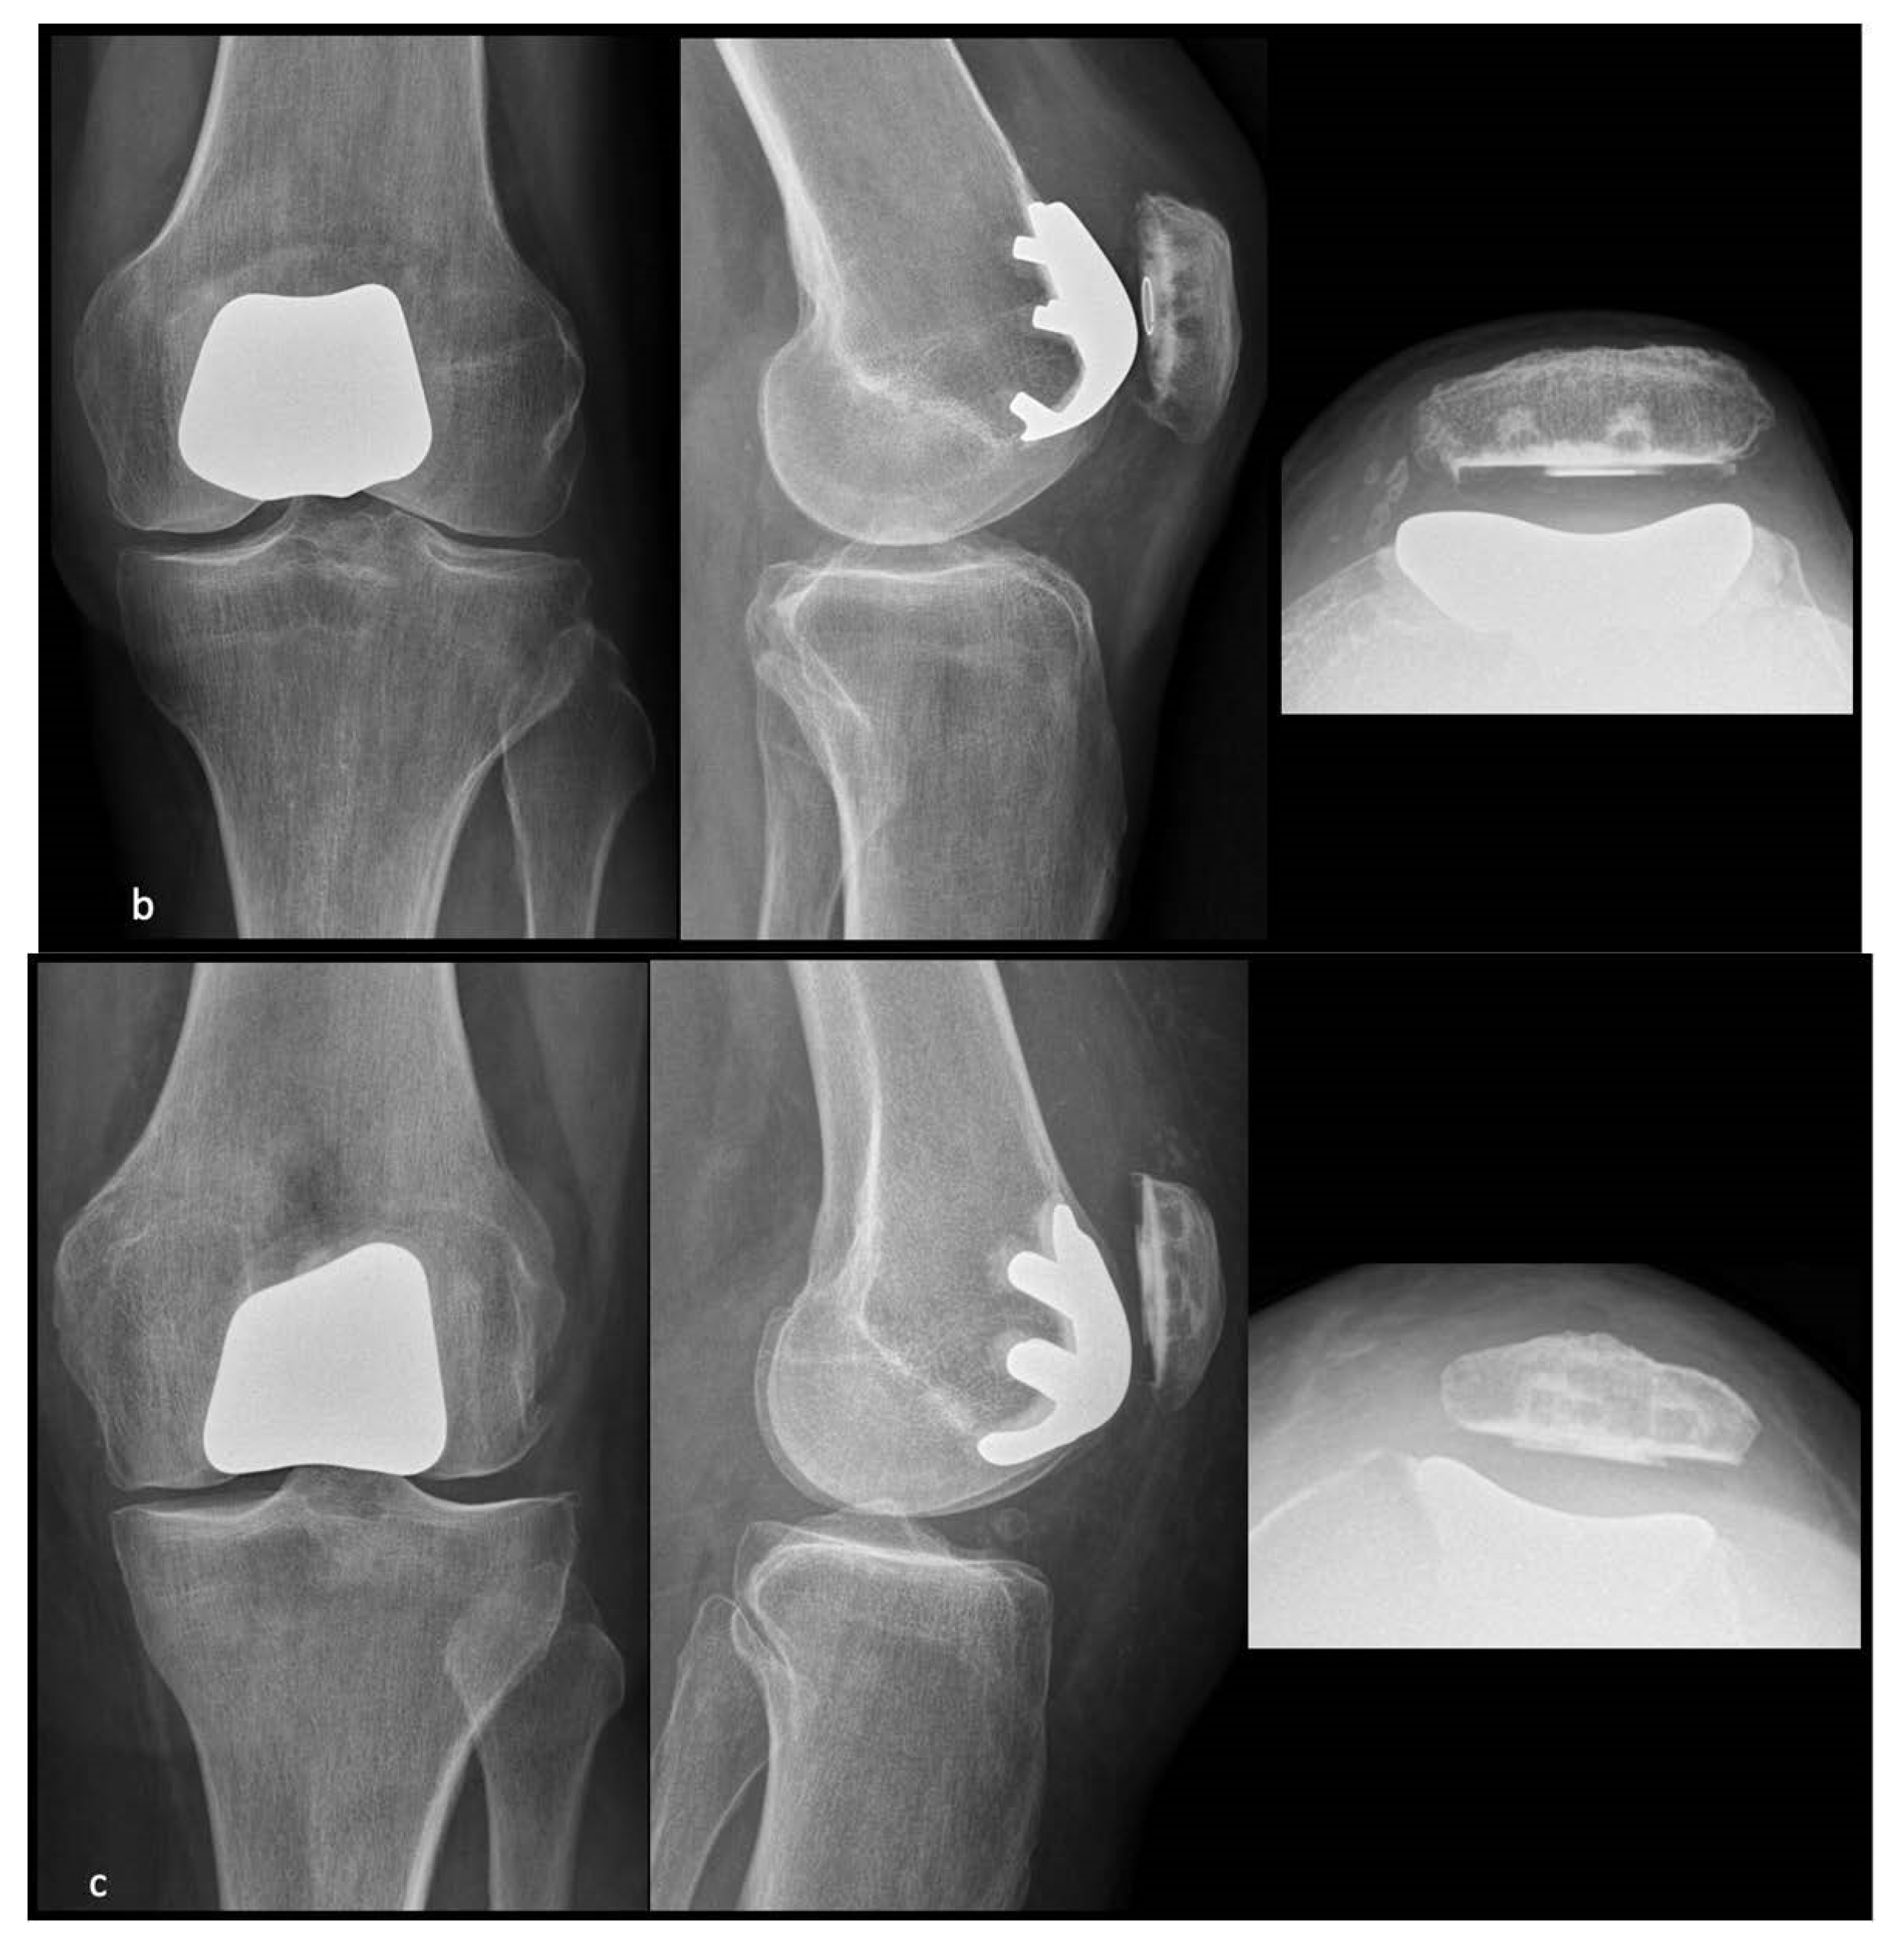

2.2. Implants